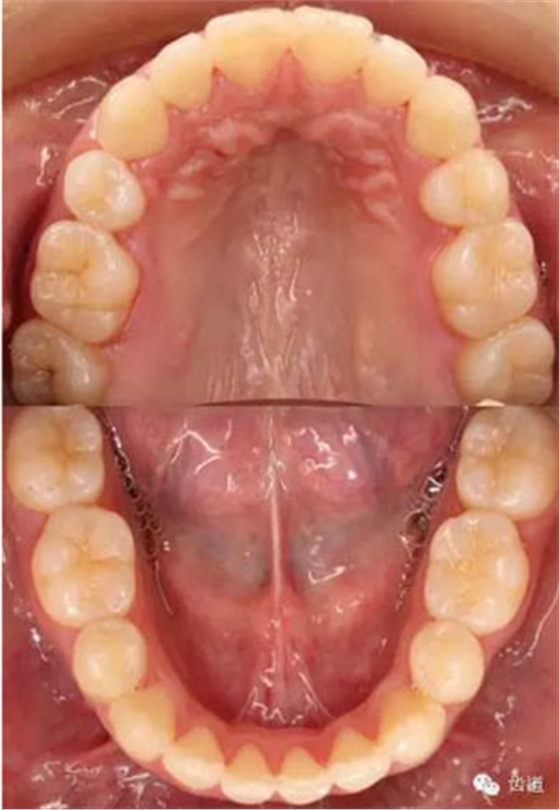

上牙弓:尖圓形,25腭側(cè)完全錯(cuò)位,26前移

下牙弓:卵圓形,下前牙區(qū)擁擠

上牙弓擁擠度9mm;下牙弓擁擠度7mm;

上牙列中線左偏1.5mm,下牙列中線右偏1mm。

Spee曲線1.5mm;前牙開合3mm;深覆蓋4mm

Bolton指數(shù):前牙比(78.8±1.72%):80.7%

全牙比(91.5±1.51%):92.9%

Pont指數(shù):

第一前磨牙指數(shù)(82.16±4.22):82.72

第一磨牙指數(shù)(63.36±3.64):64.97